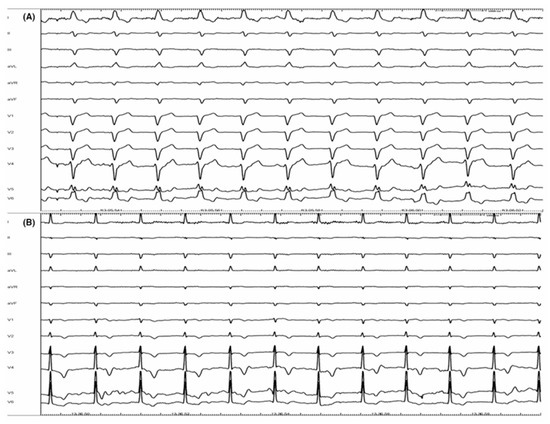

- Huang, W.; Su, L.; Wu, S. Pacing treatment of atrial fibrillation patients with heart failure: His bundle pacing combined with atrioventricular node ablation. Card. Electrophysiol. Clin. 2018, 10, 519535. [Google Scholar] [CrossRef] [PubMed]

- Huang, W.; Su, L.; Wu, S.; Xu, L.; Xiao, F.; Zhou, X.; Ellenbogen, K.A. Benefits of permanent His bundle pacing combined with atrioventricular node ablation in atrial fibrillation patients with heart failure with both preserved and reduced left ventricular ejection fraction. J. Am. Heart Assoc. 2017, 6, e005309. [Google Scholar] [CrossRef] [PubMed]